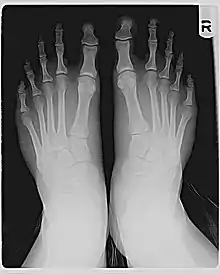

Les os métatarsiens derrière les orteils varient en longueur relative. Pour la plupart des pieds, une courbe lisse peut être tracée à travers les articulations à la base des orteils. Mais dans le pied de Morton, la ligne doit se plier plus fortement pour passer par la base du gros orteil, comme le montre le schéma. C'est parce que le premier métatarsien, derrière le gros orteil, est court par rapport au deuxième métatarsien, à côté de lui. Le deuxième métatarsien le plus long place l'articulation à la base du deuxième orteil (la deuxième articulation métatarsienne-phalangienne, ou MTP) plus en avant.

Si le gros orteil et le deuxième orteil ont la même longueur (mesurée de l'articulation MPT à la pointe, y compris uniquement les phalanges), le deuxième orteil fera saillie plus loin que le gros orteil, comme indiqué sur la photo. Si le deuxième orteil est plus court que le gros orteil, le gros orteil peut toujours dépasser le plus éloigné, ou il peut y avoir peu de différence, comme indiqué sur la radiographie.